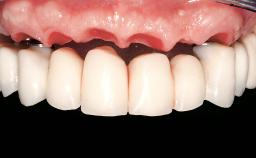

Prosthesis Type | FDP |

SAC Level | Straightforward |

Defining Characteristics | Up to three missing teeth to be replaced with an implant-borne restoration or restorations |

Loading Protocol | Conventional or early |